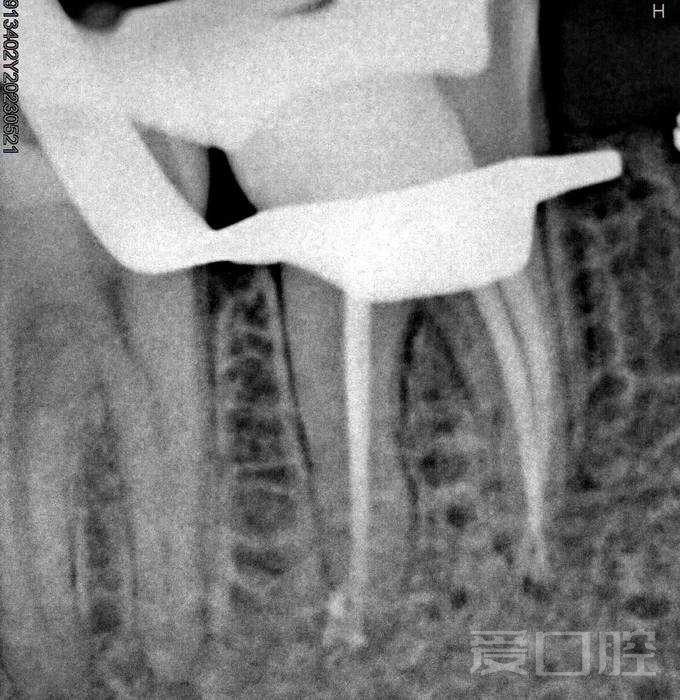

看个根充 —— 下颌第二磨牙